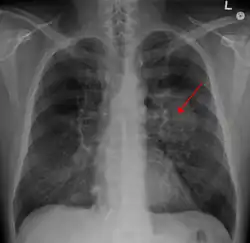

| A chest X-ray showing a tumor in the lung (marked by arrow) | |